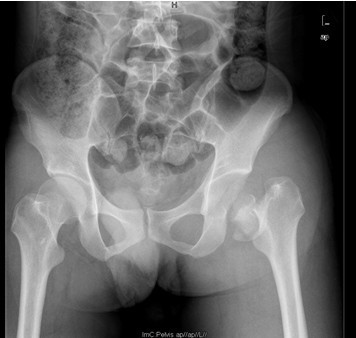

患者男,40岁,因“左股骨头股骨颈骨折切开复位内固定术后2+年”入院,患者2+年前因车祸致左股骨头、颈粉碎性骨折于我院就诊,行左股骨头股骨颈骨折切开复位空心钉+可吸收镙钉内固定术,术后恢复良好出院。术后7月后扶双拐活动。6月前患者无明显诱因出现左髋部疼痛,以负重时为重,后患者只能扶双拐活动。现患者为进一步治疗入我院。

查体:左髋外侧可见一约25cm手术瘢痕,其上可见一点状结痂,左腿较右腿短缩,左腿肌肉较右腿萎缩,步态异常。左髋部无压痛,左腿外侧感觉异常,以左膝外侧为重,左髋外侧叩击痛,左足背动脉搏动未扪及异常。左下肢较右下肢短缩约2cm,左髋关节活动受限,其余各关节未见明显异常。 辅查:MRI示左股骨头坏死

诊断:左股骨头股骨颈粉碎性骨折切开复位内固定术后坏死 治疗:择期行关节置换术